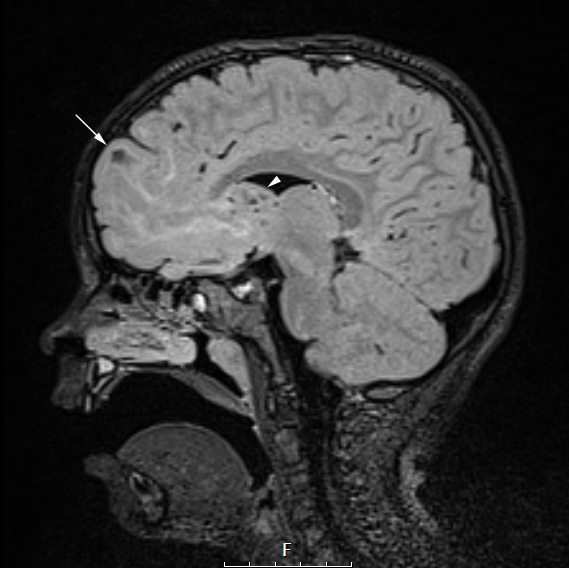

Case 16 History ---- The patient is a 4yo female with intractable epilepsy and tuberous sclerosis. Her seizures consist of focal episodes that occur 5-10 times per day. She typically stops activity, stiffens, and head or eyes turn to the left. Her current medications include clobazam, topiramate, and keppra. A recent vEEG and MRI, determined that her seizures were most likely originating from the region of the extensive right frontal dysplasia/tuber. Her case was discussed in the pediatric epilepsy conference and the consensus was to perform a right frontal lesionectomy which would involve resection of the right frontal lobe anterior to the motor strip and possibly including removal of a nearby SEGA. She is active and playful, but her seizures interfere with her school and activity. She was admitted for resection of her right sided lesions. (This is the same case as SEGA Case 21) ---- 16A1 This FLAIR scan shows the cortical epileptogenic tuber (arrow) which was subsequently surgically removed and the right ventricular SEGA (arrowhead).